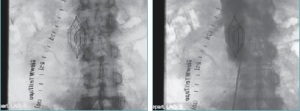

VascuTape – radiopákní značící páska LeMaitre Vascular – poskytuje vysokou přesnost během vaskulárních procedur. Implantace stentu, PTA, odstranění aterosklerotického plátu, a další procedury se pomocí inovativních zobrazovacích pásek provádějí snadněji a přesněji. VascuTape byla vyvinuta praktikujícím cévním chirurgem a je ceněna pro svou přesnost , jednoduchost, a pohodlnost.

LeMaitre Stent Guide má MILIMETROVÉ ZNAČENÍ (270 mm) pro větší přesnost a správnost při určování velikosti a umisťování stentu.

NOVÝ 550 mm LeMaitre Stent Guide má MILIMETROVÉ ZNAČENÍ (550 MM) a nabízí delší referenční délku přesnosti a správnosti při určování velikosti a umisťování stentu.

LEMAITRE® STENT GUIDE

IMPLANTACE STENTU Chirurg může přesněji určit potřebnou velikost stentu, a opakovatelné orientační body jsou k dispozici pro

roztažení stentu. LeMaitre Stent Guide (270 mm) má milimetrové značení pro větší přesnost a správnost při určování velikosti a umístění

STENTING KAROTID Operatér může přesněji určit velikost potřebného stentu. Opakovatelné orientační body jsou k dispozici pro

roztažení balónku, čímž zajišťují úspěšnou proceduru a minimalizují spotřebu angiografického barviva.